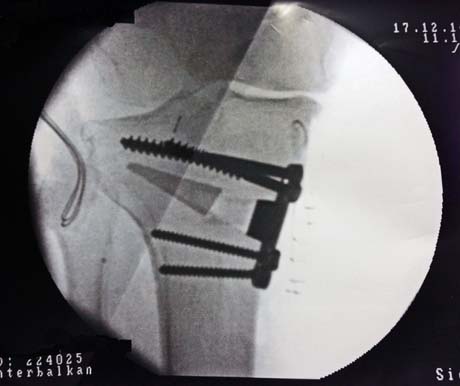

Η μέτρηση του μηχανικού άξονα του κάτω άκρου κατά τη διάρκεια της χειρουργικής επέμβασης και με την υποβοήθηση του ακτινοσκοπικού μηχανήματος είναι απαραίτητη για την διόρθωση αυτού (κόκκινη γραμμή αποτελεί την ράβδο που ελέγχει τη διόρθωση του μηχανικού άξονα διεγχειρητικά)

Τοποθέτηση ειδικής πλάκας οστεοτομίας (οστεοτομία βλαισότητας της κνήμης). Στο κενό του οστού εφαρμόζονται αλλομοσχεύματα και αυτομοσχεύματα

Ακτινολογικός έλεγχος αμέσως μετά το χειρουργείο